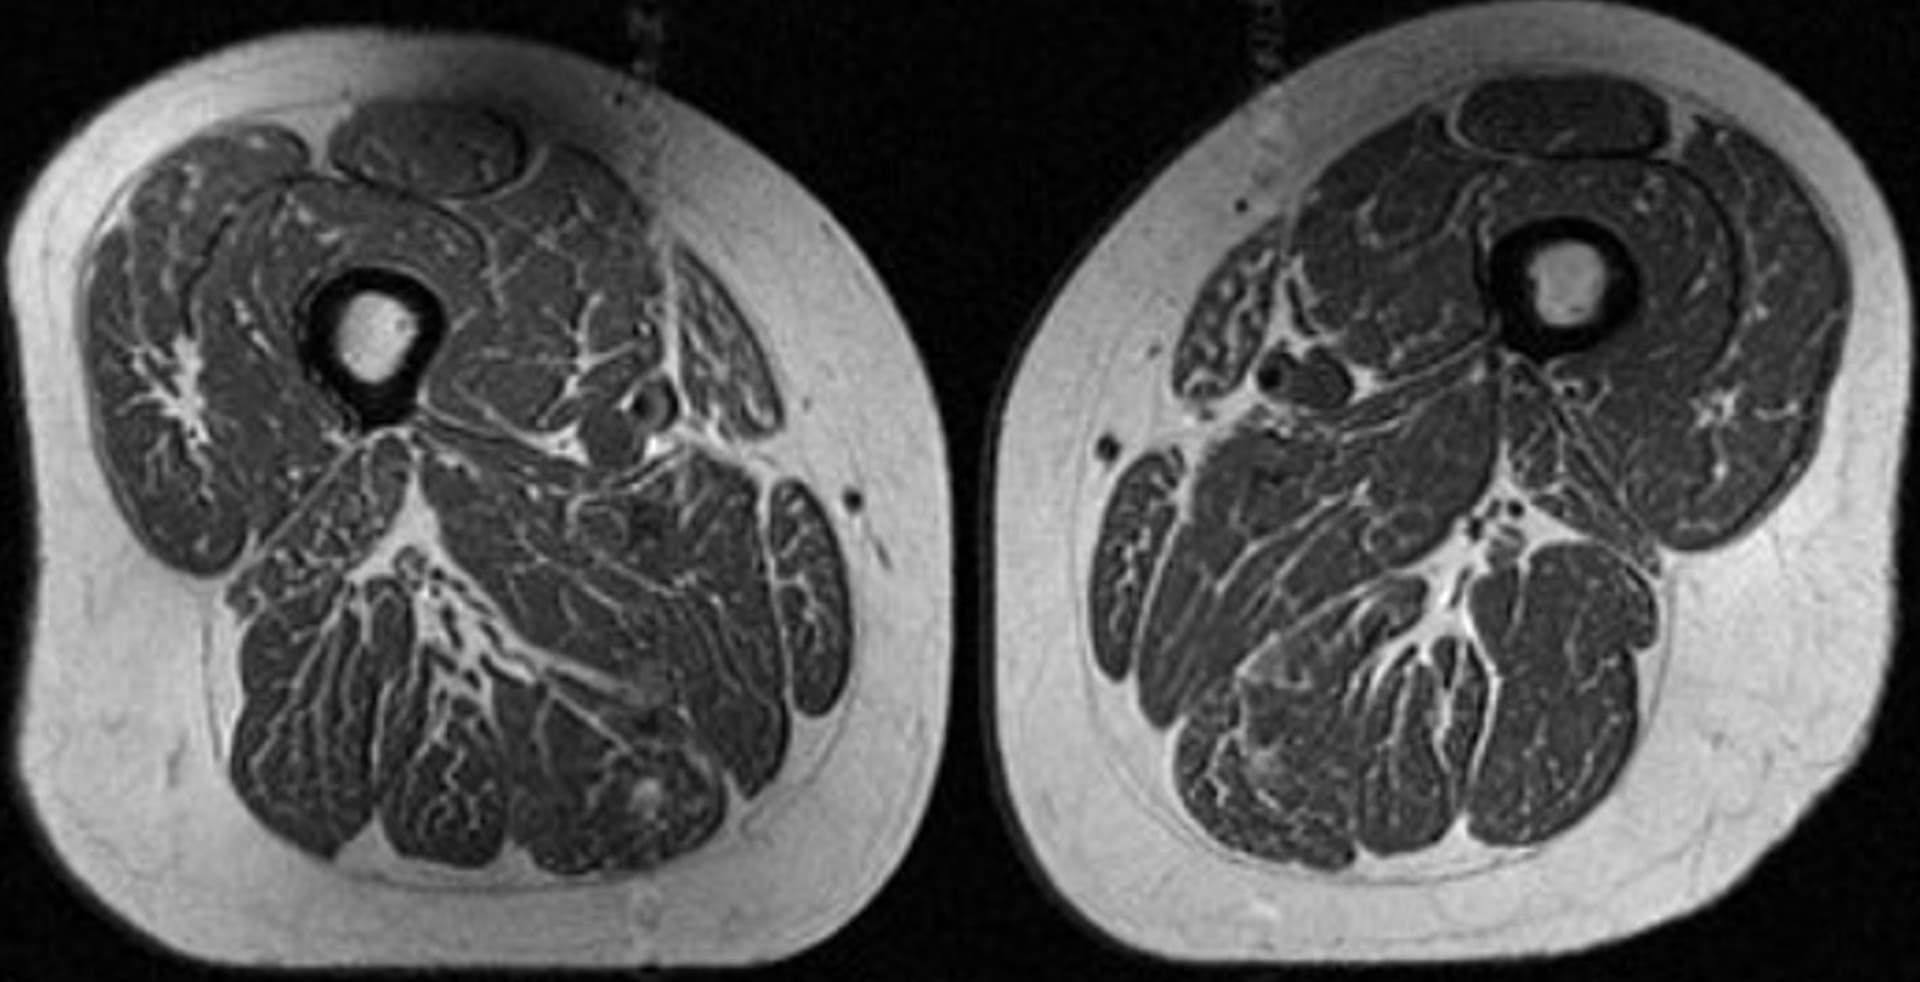

لكن تُظهر هذه الصورة تصويرًا بالرنين المغناطيسي (MRI) لفخذ امرأة تبلغ من العمر 62 عامًا، كانت تحصل على 87% من سعراتها الحرارية السنوية من الأطعمة فائقة المعالجة.

وأوضحت أكّايا، المؤلفة الرئيسية لدراسة جديدة حلّلت تأثير الأطعمة فائقة المعالجة على الدهون داخل العضلات لدى أشخاص معرضين لخطر هشاشة مفصل الركبة، أنّ الخيوط الدهنية الخفية المتغلغلة بين ألياف العضلات وداخلها قد تكون مؤشرًا على مشاكل صحية خطيرة.

كما أظهرت امرأة أخرى في الدراسة، تبلغ من العمر 61 عامًا، وجود ترخيم دهني في عضلات فخذها، لكنه كان أقل حدة، إذ شكّلت الأطعمة فائقة المعالجة نحو 29% من نظامها الغذائي السنوي.

وقالت أكّايا: "كان ذلك مقلقًا لأنّ هؤلاء الأفراد الذين خضعوا للتصوير في وقت لم تظهر لديهم فيه أي علامات على التهاب الركبة، كانوا بالفعل يُظهرون تدهورًا في جودة العضلات".

كانت المرأة البالغة من العمر 61 عامًا، التي شكّلت الأطعمة فائقة المعالجة 29.5% من نظامها الغذائي (في الصورة A)، تمتلك مؤشر كتلة جسم أعلى قليلًا بلغ 32.6، وتمارس نشاطًا بدنيًا أقل بكثير من المرأة الأخرى (في الصورة B) التي بلغ مؤشر كتلة جسمها 31.8، وشكّلت الأطعمة فائقة المعالجة 87.1% من نظامها الغذائي.

ومع ذلك، أظهرت المرأة ذات الاستهلاك الأعلى لهذه الأطعمة ترخيمًا دهنيًا أكبر بكثير في عضلات فخذها.